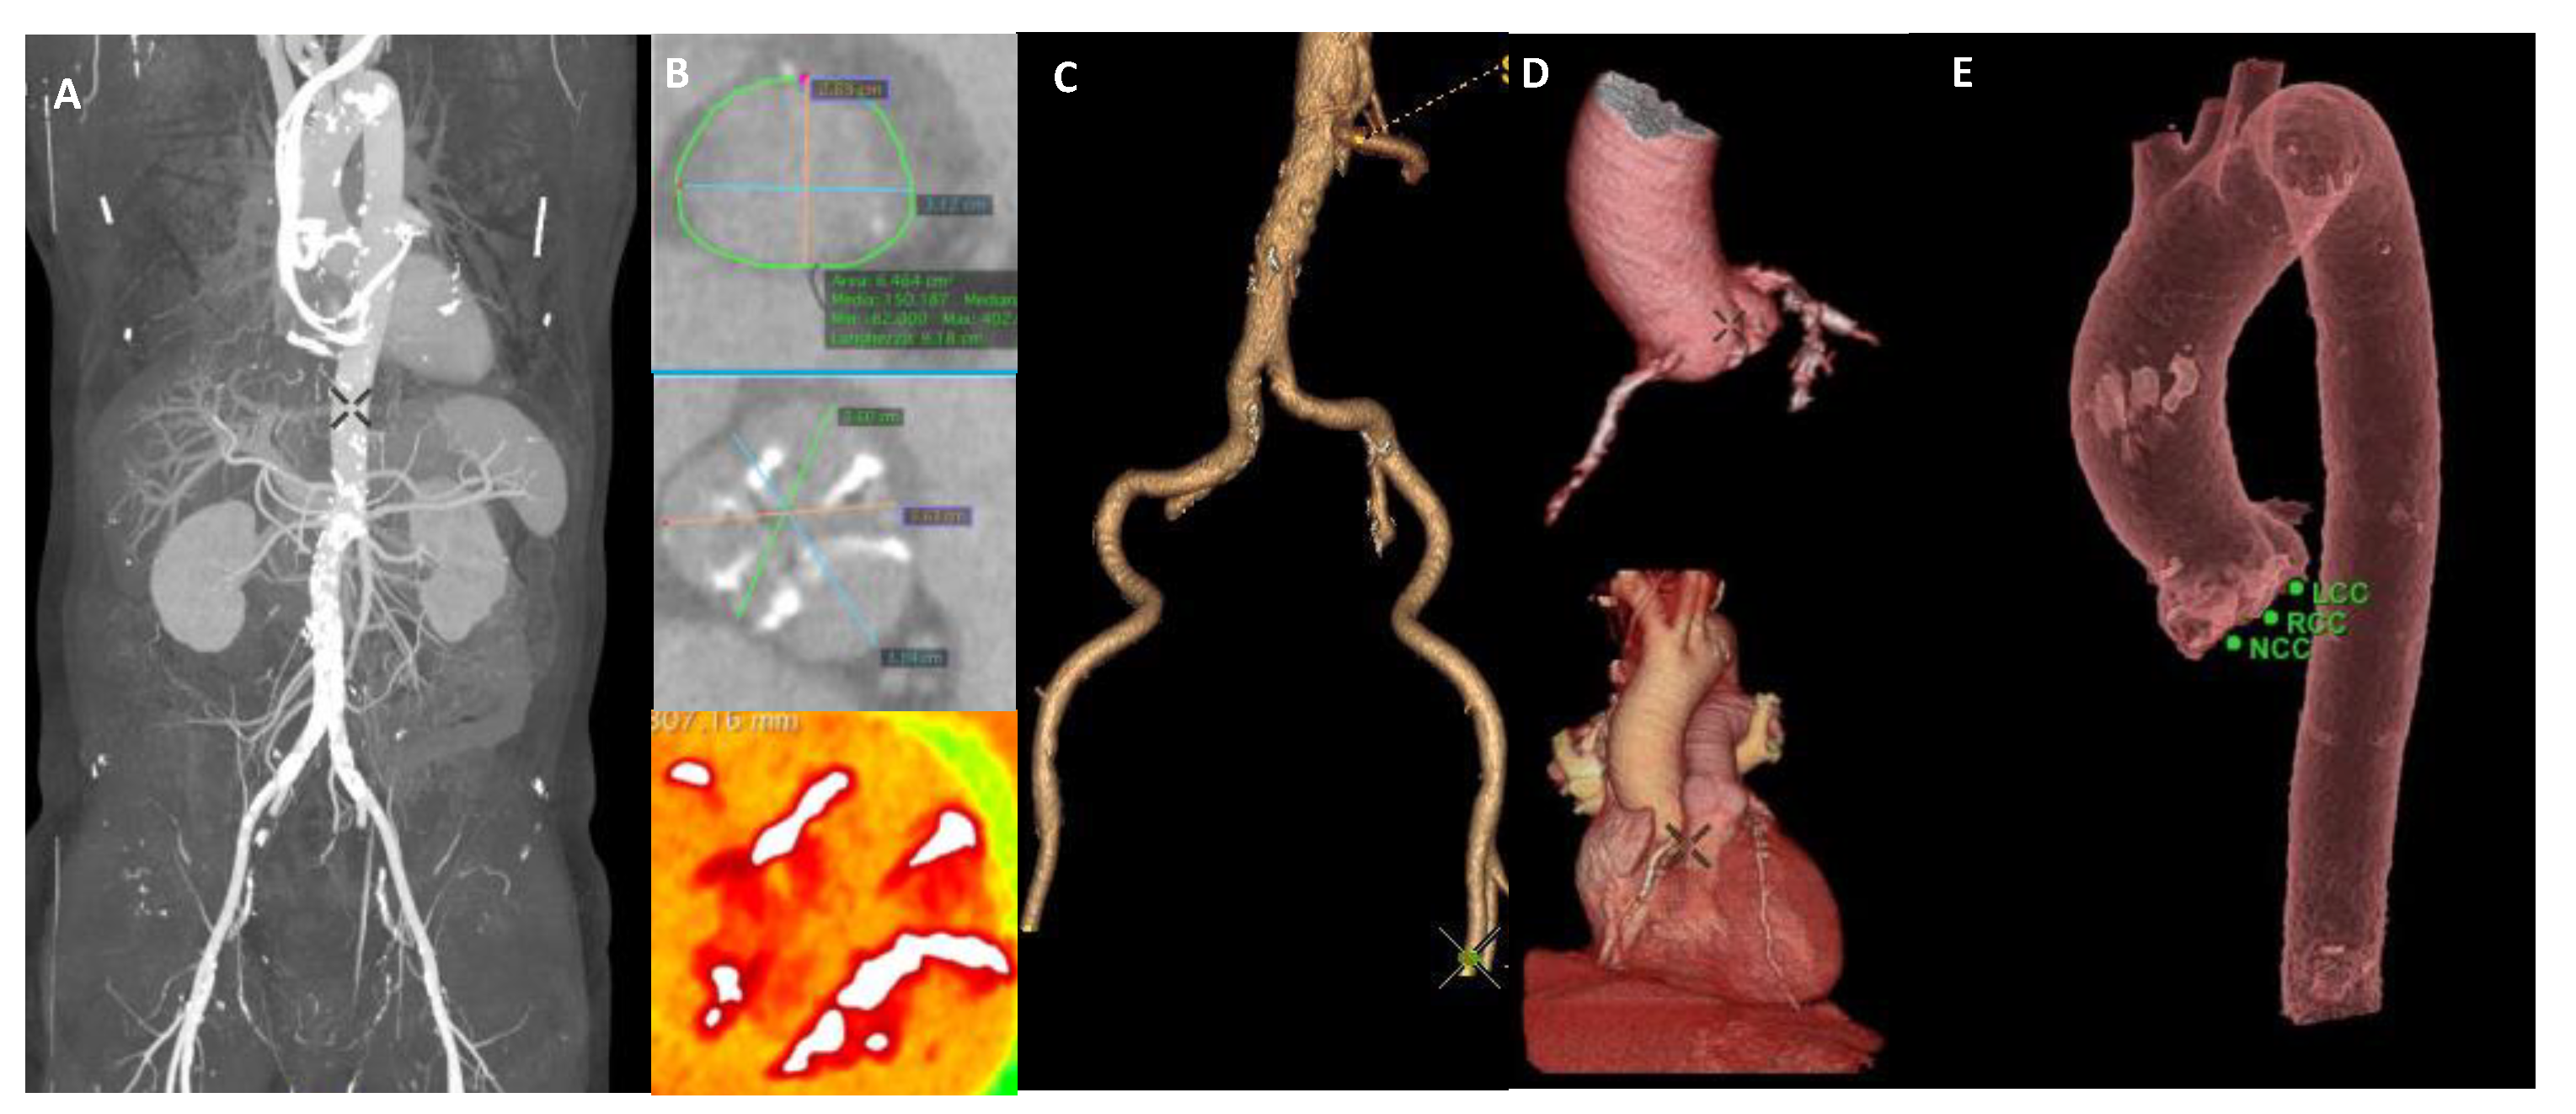

- Mangieri, A.; Laricchia, A.; Montalto, C.; Palena, M.L.; Fisicaro, A.; Cereda, A.; Sticchi, A.; Latib, A.; Giannini, F.; Khokhar, A.A.; et al. Patient selection, procedural planning and interventional guidance for transcatheter aortic valve intervention. Minerva Cardiol. Angiol. 2021. [Google Scholar] [CrossRef]

- Yucel-Finn, A.; Nicol, E.; Leipsic, J.A.; Weir-McCall, J.R. CT in planning transcatheter aortic valve implantation procedures and risk assessment. Clin. Radiol. 2021, 76, e71–e73. [Google Scholar] [CrossRef]